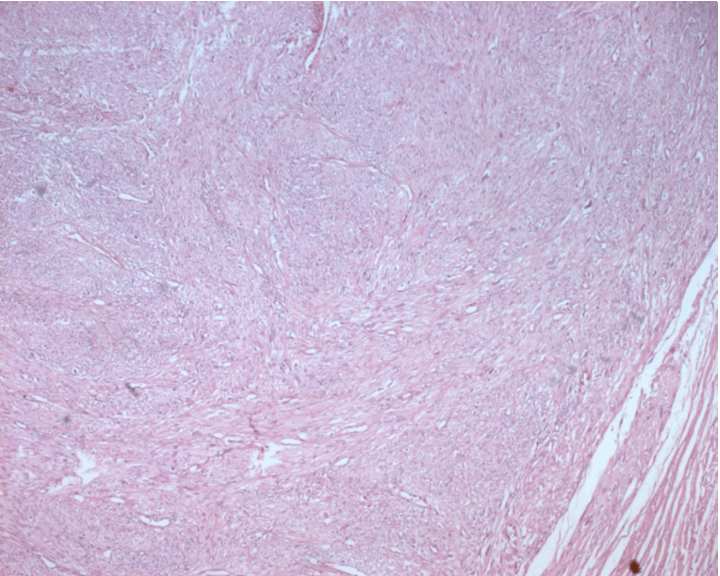

Microscopic examination showed a high degree of cellular proliferation composed of spindle cells with round or oval-shaped nuclei implicating a storiform growth pattern (Figure 1). Necrosis was evident. Immunohistochemical examination revealed that the tumor cells were strongly positive for calponin, epithelial membrane antigen (EMA) smooth muscle actin and vimentin (Figure 2) and (Figure 3) but negative for S-100 and myogenic regulatory protein (MyoD1) proteins. The combined histologic and immunohistochemical findings were diagnostic of primary high-grade intratesticular leiomyosarcoma. With 24 months of follow-up, which included computed tomography scan of the abdomen, pelvis, bone, and chest, the patient remained free of disease.

Figure 1: Diffuse mesenchymal proliferation of malignant spindle shaped cells with eosinophilic, fibrillary cytoplasm and atypical nuclei displaying mitotic figures (H&E stain, x100).